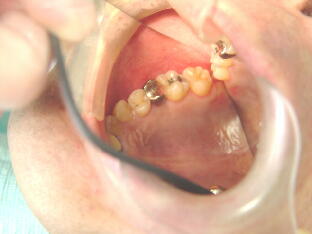

上下顎の第二大臼歯は虫歯になって神経がしんだ場合、根管治療が大変困難で根尖病巣

やのう胞が生じやすい場所です。下の写真は第二大臼歯が保存困難のため抜歯になり、そ のままだと相対する歯が歯の無い所に挺出してくるので、通常は延長ブリッジや部分入れ 歯等になるのですが、親知らずを有効利用し矯正移動させた症例です。 ![]() ![]()

上の写真は埋っていた親知らずを切開して歯冠部をだし、移動させた症例です。